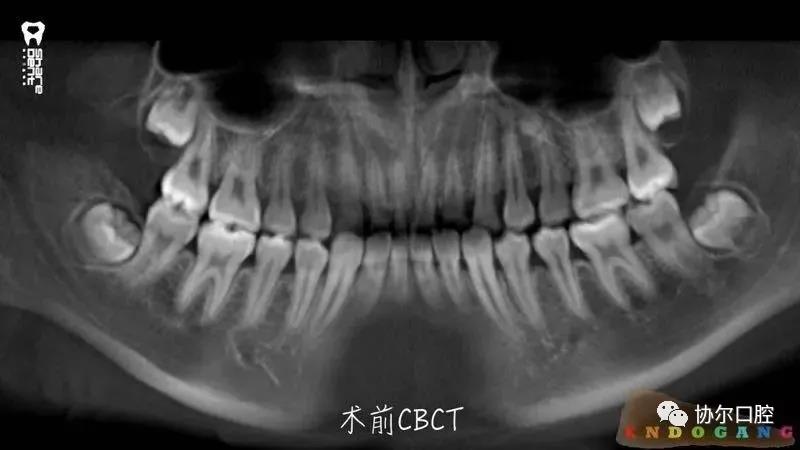

好多朋友都在问有没有前牙外伤折断后美塑树脂断牙显微再接的病例,正当小编“愁眉苦展”时,喻刚老师雪中送炭来了。15岁青少年断牙24小时,破镜重圆,修旧如旧。

病例刷一波